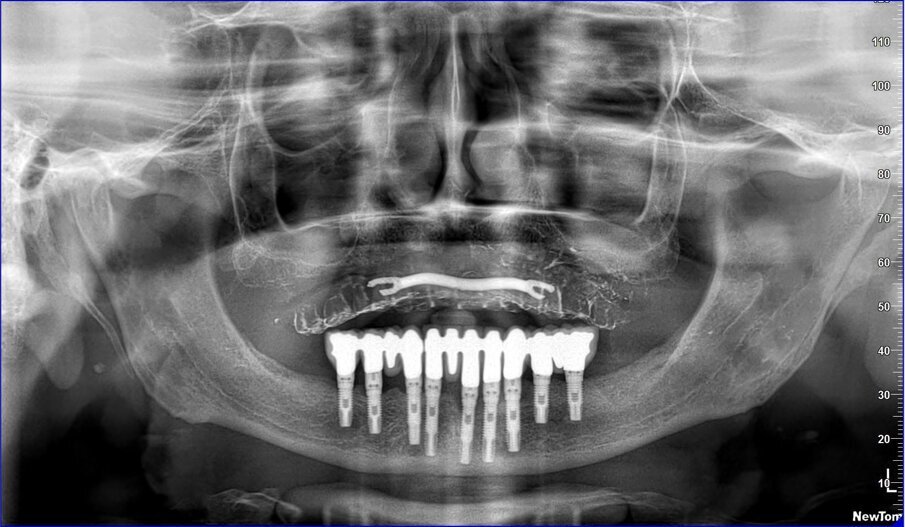

La resina alla stato ancora tenero va indurita con la lampada polimerizzante per alcuni minuti; una volta controllata la masticazione anche senza la chiave articolare e fatti gli opportuni minimi ritocchi, la protesi va rimossa e rifinita a dovere, poi riaccoppiata. Una OPT di conferma serve per verificare il corretto alloggiamento delle cappette sui monconi e la passività del manufatto.

Le tabelle 1-8 mostrano, su un totale di 313 impianti eseguiti tra arcata superiore (208) e inferiore (105), che la tecnica non ha alcuna complicanza biologica a 3 anni di esecuzione, non sono stati evidenziati fallimenti implantari in arcata inferiore (18 pazienti), solamente 5 in arcate superiori tutti nella zona molare (29 pazienti). In 1 paziente è stata registrata una frattura della protesi dovuta a eccessiva distanza tra gli impianti (zona laterale superiore e tuberosità) con antagonista naturale senza presenza di molari; 3 fratture dei denti in pazienti con bruxismo e serramento; circa la metà dei casi (140 impianti) è stata eseguita in condizione post-estrattiva e alcuni casi sono stati caricati con metodiche avanzate di rialzo di seno mascellare (11 pazienti) e 1 con Split Crest. Tutti gli impianti sono stati caricati immediatamente, anche quelli nei settori posteriori superiori o nella tuberosità.